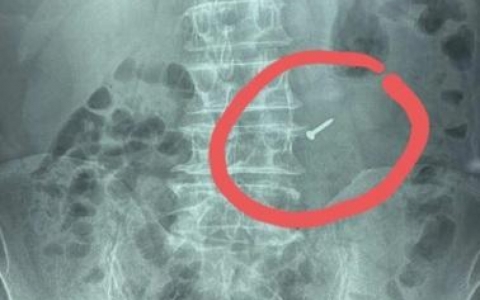

Nam bệnh nhân bị cây đinh trôi tuột xuống dạ dày vì thói quen khó bỏ

Ông N. ở Đà Nẵng có thói quen ngậm cây đinh trong miệng khi đóng đồ gỗ. Trong quá trình làm việc, cây đinh trôi tuột xuống cổ họng và trôi xuống dạ dày...